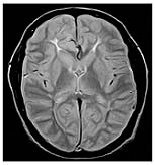

Each echo is used to create a different image, usually displaying different image contrast. The images below were acquired using a Spin Echo variable echo sequence. The first echo displays PD-weighting, while the second echo displays T2-weighting.

| 1 | First echo |

| 2 | Second echo |

PD-weighted images have contrast that is primarily due to the density of protons in the structures. PD-weighted images result when you select scan timing parameters that minimize the T1 (long TR) and the T2 (short TE) contrast effects. With PD-weighted images, tissues with a greater number of protons are bright and tissues with fewer protons are dark. In the brain, gray matter is brighter than white matter, due to the amount of protons it contains.

PD- and T2-weighted images can be produced in the same acquisition using two echoes because the TR requirements are compatible.